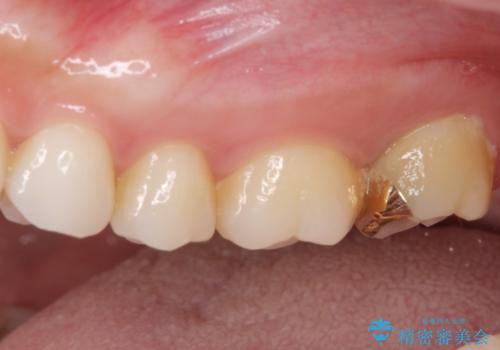

- 奥歯にフロスが引っかかるようになり、虫歯ではないかとのことで来院された患者様です。

レントゲン写真より、1番奥の歯に虫歯があることが分かりました。

奥で目立たないことから、虫歯の再発リスクが最も低く、咬合力による歯への負担も少ないゴールドインレー(PGAインレー、白金加金インレー)にて修復治療をすることとしました。